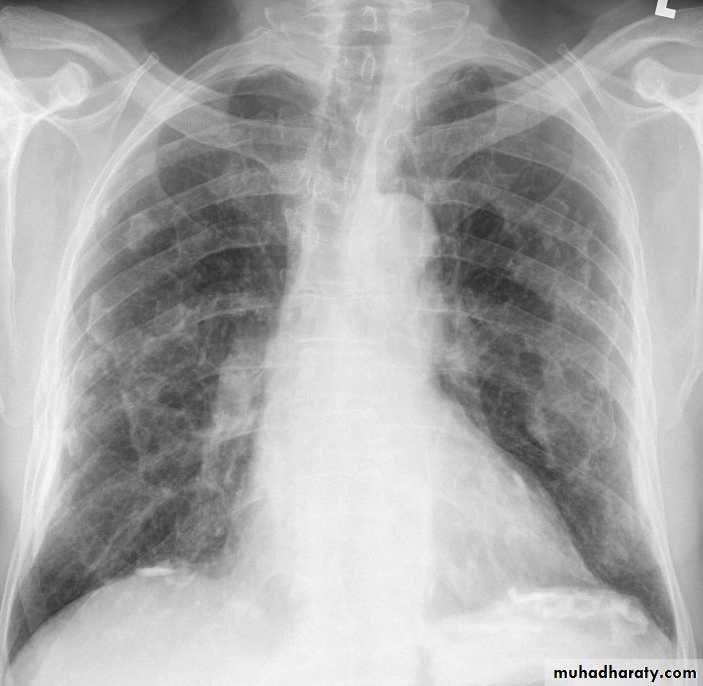

Is a diffuse interstitial fibrosis of the lungs that may or may not be associated with pleural fibrosis due to exposure to fibrous mineral asbestos.Requires substantial exposure over several years

Risk factor for carcinoma of the lung and larynx

Exertional breathlessness and fine, late inspiratory crackles over the lower zones and digital clubbing.

Chest X-ray; Shows bi-basal reticular nodular shadowing and asbestos-related pleural disease is usually present. HRCT scanning is more sensitive.

Pulmonary function tests; Typically show a restrictive defect with decreased lung volumes and reduced gas transfer factor.